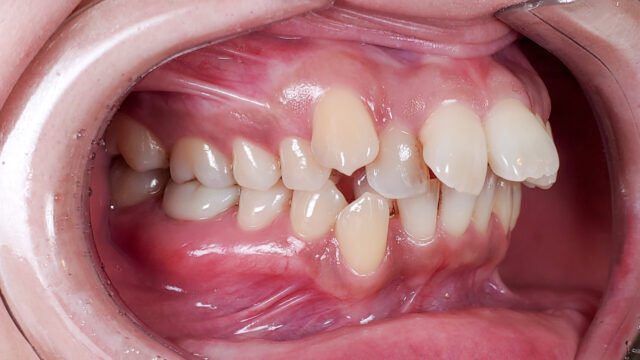

Before

矯正開始前

右上小臼歯・右下前歯を1本ずつ抜歯し、マウスピースによる矯正治療開始。